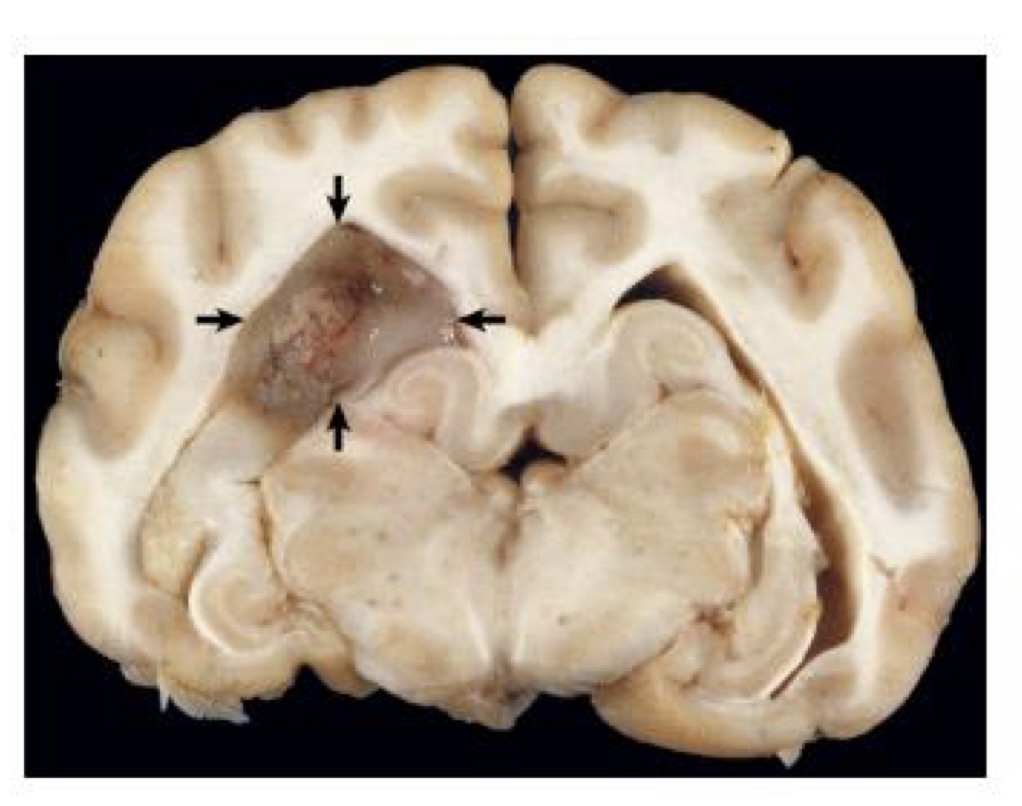

what is this?

oligodendroglioma → tumor is gray, soft, and gelatinous